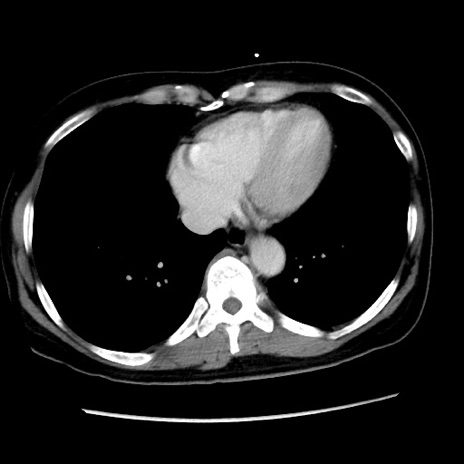

冠状断像